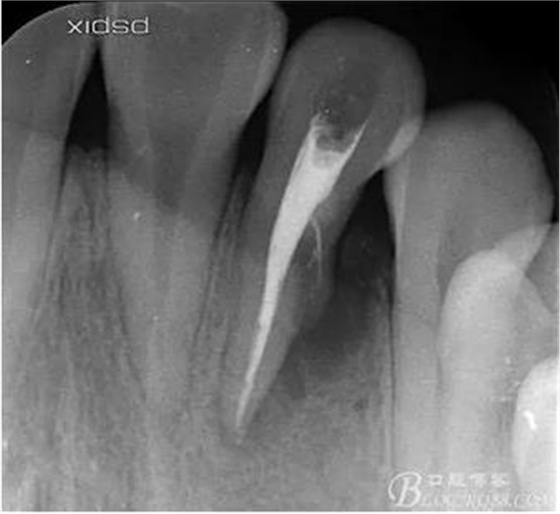

(1)檢查:12唇側(cè)牙齦可見竇道,牙體顏色較鄰牙暗,無光澤,形態(tài)完整無缺損,唇側(cè)及近遠(yuǎn)中向未提及牙周袋。腭側(cè)齦緣輕度紅腫,舌側(cè)窩可探及裂溝,可見浸墨狀痕跡,沿裂溝舌側(cè)探診牙周袋深大于11mm,除患牙外全口牙周狀況良好,為探及牙周袋,牙齦色粉紅。邊緣菲薄,質(zhì)地堅韌。12冷熱診無反應(yīng),叩診(+-),無明顯松動,無咬合創(chuàng)傷。12根尖x線片示,根管中三分之一中可見一斜向線樣透射影像根尖區(qū)及遠(yuǎn)中根三分之一可見低密度透射暗影,錐形束CT示12根尖區(qū)唇腭向骨吸收已穿通,根面溝達(dá)根中三分之一卷曲分出另一牙根,再未見其他明顯的根管系統(tǒng)。